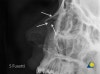

Nasal lateral 사진을 찍으면 위 사진처럼 골절선이 보일 수도 있습니다. 골절선이 애매한 경우도 많습니다.

X-ray : 코뼈 골절(Nasal fracture)